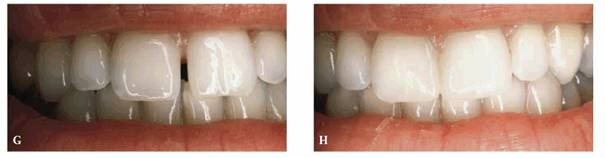

TREATMENT: The mandibular incisors were adjusted to eliminate anterior

interference and traumatic occlusion, followed by initiation of periodontal

therapy. On completion of conservative periodontal therapy, an elastic ligature

was placed around the maxillary central incisors to close the diastema. After

wearing the elastic for several days, the patient returned with the space

closed (Figure 23-5B

Figure 23-5B: After conservative periodontal therapy and occlusal equilibration, a rubber elastic was placed on the central incisors to close the diastema.

To prevent future drifting of the central incisors and reformation of the

diastema, the newly created space between the central and lateral incisors must

be treated. Artus's shim-type articulating ribbon (

The addition of a single increment of composite resin is next adapted to the lateral incisor to close the diastema. This material is then polymerized (Figure 23-5D) labially and lingually. Lastly, the patient is instructed in the use of thin dental floss to properly cleanse the interdental spaces.

Figure 23-5C and D: The adjacent lateral incisors were tightly bonded using Artus shim stock (5/10,000th inch thick) to achieve the tightest closure possible.

RESULT: Figure 23-5E shows the closed diastema,

sufficiently stabilized by the lateral incisors. Regardless of whether the

lateral incisors were crowned, laminated, or bonded, it is essential that the

contact area be broad so that the central incisors are held firmly in place.

During closure, it is recommended to stabilize the central incisors with

digital pressure while the composite resin is being applied and until it is

polymerized.

Figure 23-5E: After 24 months, the teeth continue to be held in position by the tightly bonded lateral incisors.